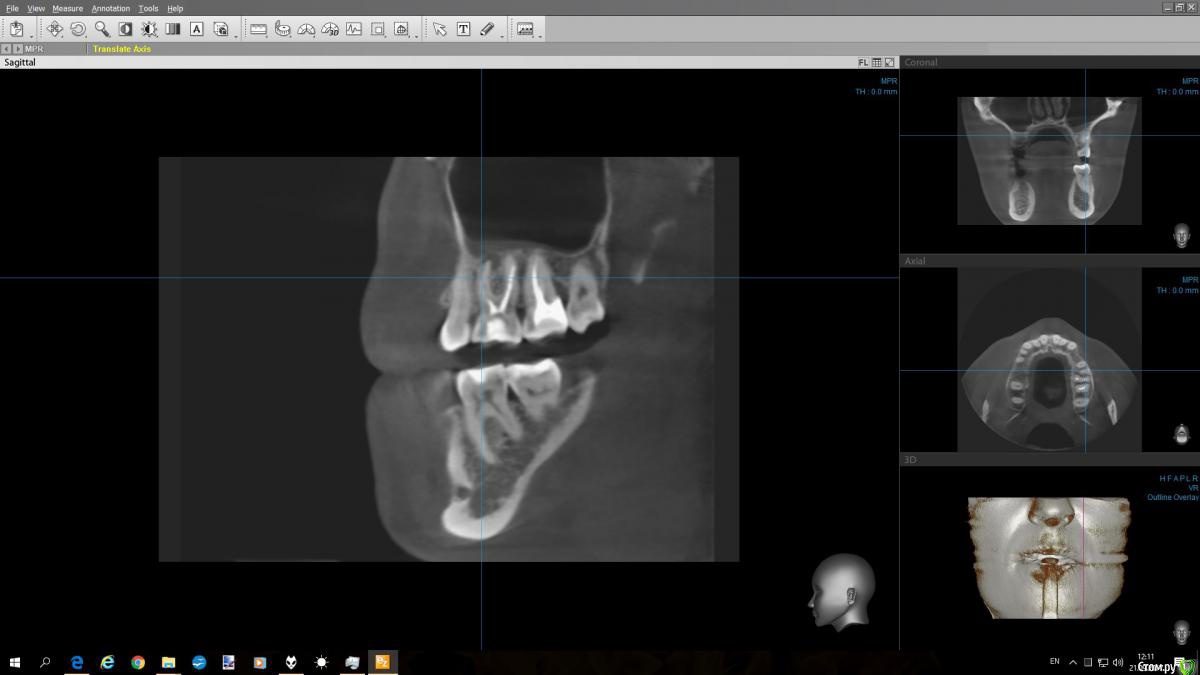

С кастрюлькой Опубликовано 21 сентября, 2017 Автор Поделиться Опубликовано 21 сентября, 2017 (изменено) Добрый день! Во вложении снимок этого зуба, как смогла выделила.. Можно ли будет дать ответ ? Изменено 21 сентября, 2017 пользователем С кастрюлькой Ссылка на комментарий

wladdX Опубликовано 21 сентября, 2017 Поделиться Опубликовано 21 сентября, 2017 (изменено) скриншоты Изменено 21 сентября, 2017 пользователем wladdX Ссылка на комментарий

DmitrySH Опубликовано 21 сентября, 2017 Поделиться Опубликовано 21 сентября, 2017 Удаляйте Ссылка на комментарий

red_butler Опубликовано 22 сентября, 2017 Поделиться Опубликовано 22 сентября, 2017 + 1 удалять Ссылка на комментарий